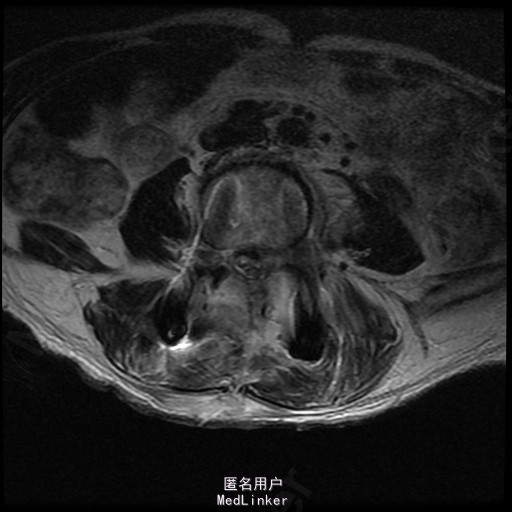

查体:左侧小腿外侧、足背感觉减退,右侧正常,双侧屈髋、伸膝、踝背伸肌肌力5级,左侧踇背伸、跖屈肌肌力4级,右侧踇背伸、跖屈肌肌力4-5级,双侧巴氏征阴性,直腿抬高试验左侧30°阳性,右侧阴性。 辅助检查: X-ray:腰椎退行性变,腰椎节段性性不稳 MR:腰椎间盘突出,腰3/4,4/5,腰4/5节段明显

随访 术后患者下肢麻木感觉较前好转,左侧踝背伸、跖屈肌力4级+,左侧肢体抬高试验阴性。术后MR检查减压彻底 讨论:1、腰椎椎管狭窄手术指证的把握,腰椎后路手术,腰椎椎间融合与椎板减压的选择? 2、术中探查如无明显间盘突出,以椎管骨性狭窄为主,可行腰椎后路椎板减压为主。